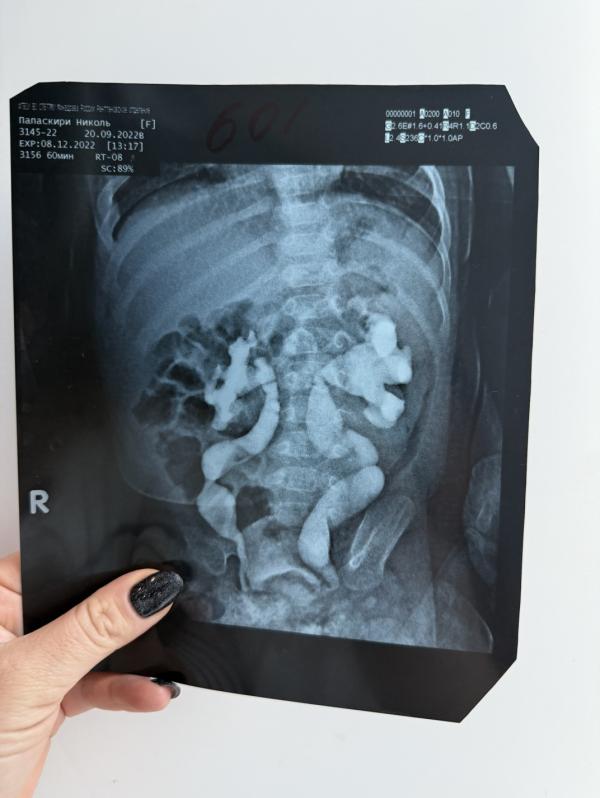

1. Снимок когда мы родились и в декабре сделали обследование .8.12.2022

2. Снимок видно какой мочеточник извилистый , длинный, у трех месячного ребенка …